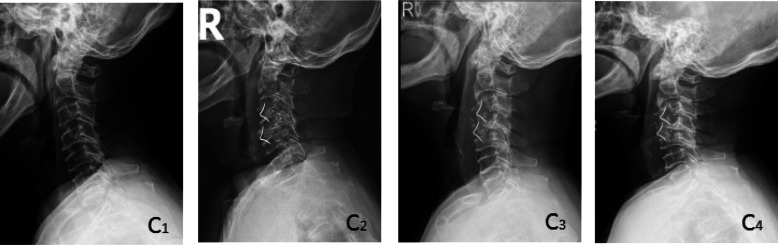

Fig. 3.

A 70-year-old female in group C with cervical spondylotic myelopathy. The preoperative VAS score, JOA score and NDI score were 5, 7, and 40% respectively, and the postoperative VAS score, JOA score and NDI score were 1, 13, and 20%, respectively. The postoperative Odom score was “excellent.” The symptoms of the patients improved obviously and there was no obvious discomfort. Brantigan score: 1, vertebral collapse, cage subsidence. C1 was preoperative X-ray plain film of the cervical spine, C2 was X-ray plain film immediately after operation, C3 and C4 were lateral plain film of the cervical spine at 3 and 6 months after operation, respectively